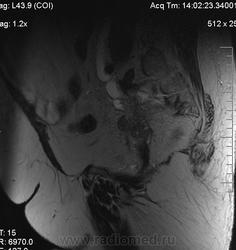

очень характерная картина для метастаза рака яичника, к сожалению.

Не могу достоверно определить локализацию метастаза брюшной полости, вероятно в лимф. узел с инвазией оободочной кишки. Рецидив С-r левого яичника думаю, что с инфильтацией левой стенки прямой кишки и культи влагалища, вторичная лимфаденопатия л/у малого таза. каликопиелоуретероэктазия (инвазия нижних отделов левого мочеточника?) Холедох широковат, но желтухи по внешнему виду нет.

Прорастание левого мочеточника рецидивной опухолью есть 100%, метастаз в большой сальник характерен для рака яичников, как и сигнальные характеристики его. Культя в данном случае шейки матки.